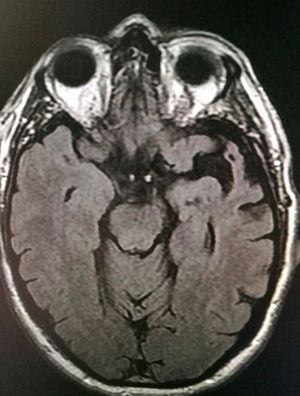

Imaging for brain

Semantic dementia , carefully evaluate the both hemisphere